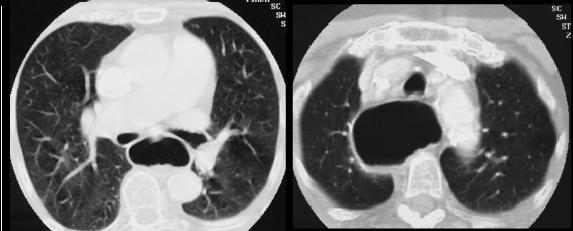

chaussette . Image TDM en fenetre parenchymateuse pulmonaire

,se donne des images si net de oesophage en coupe axiale ,

sagitale et de frontale ( voie image )

Mega oesophage : image radiologique

TDM fenetre parenchymateuse en coupe axiale |